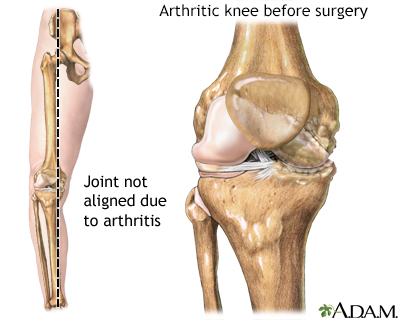

Severe cases of OA might benefit from surgery to replace or repair damaged joints. Options include:

- Changing the alignment of a bone to relieve stress on the bone or joint (osteotomy)

- Total or partial replacement of the damaged joint with an artificial joint (knee replacement, hip replacement, shoulder replacement, ankle replacement, and elbow replacement)